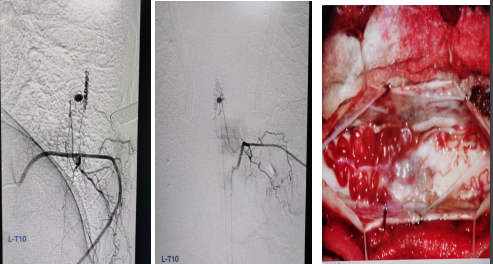

病例1

患者女,41岁。突发双下肢无力6小时。

答案:脊髓血管畸形并出血。造影及手术结果如下。

脊髓出血发病急,临床少见,血管畸形是脊髓出血的主要原因。主要表现为剧烈胸腰背部疼痛及截瘫,感觉障碍及括约肌功能障碍。脊髓出血与急性脊髓炎、脊髓梗死相互鉴别。脊髓炎发病前可有呼吸道或消化道感染等诱因,神经根刺激症状不明显,MRI检查可见T2WI横贯性的异常高信号。脊髓梗死可急性或亚急性发病,多发生在中老年人,以脊髓前动脉梗塞多见,运动障碍明显,感觉障碍轻微或缺失,MRI检查T2WI像可见脊髓前动脉供血区高信号,后索多不受累。

病例2

患者女性,41岁,间歇性双下肢无力2月,小便费力1月。

答案:脊髓硬脊膜动静脉瘘(SDAVF)。SDAVF是最常见的脊髓血管畸形,多累及胸腰段,占脊髓血管畸形的70%。本病中老年男性多见,多缓慢起病,并进行性加重,少数呈急性起病,临床确诊较难。临床表现步态异常、下肢乏力、感觉障碍、疼痛,伴或不伴括约肌功能障碍等。症状不典型时可误诊为周围神经病等,如表现为单侧下肢无力。表现为双足袜套样感觉异常时会误诊为糖尿病周围神经病等。表现为下肢放射性疼痛时被误诊为退行性脊椎疾病。脊髓MRI:T1示肿胀的脊髓呈低信号影,伴有弥漫性增强; T2呈多节段脊髓中央部高信号(大白萝卜样);脊髓背侧多有环状低信号(提示扩张、扭曲的静脉血管,呈小黑芝麻样)。